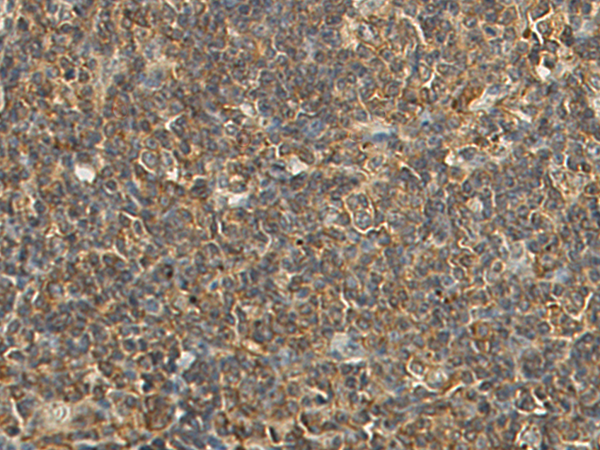

IHC positive control: |

Human lung cancer and Human tonsil |

IHC Recommend dilution: |

50-200 |